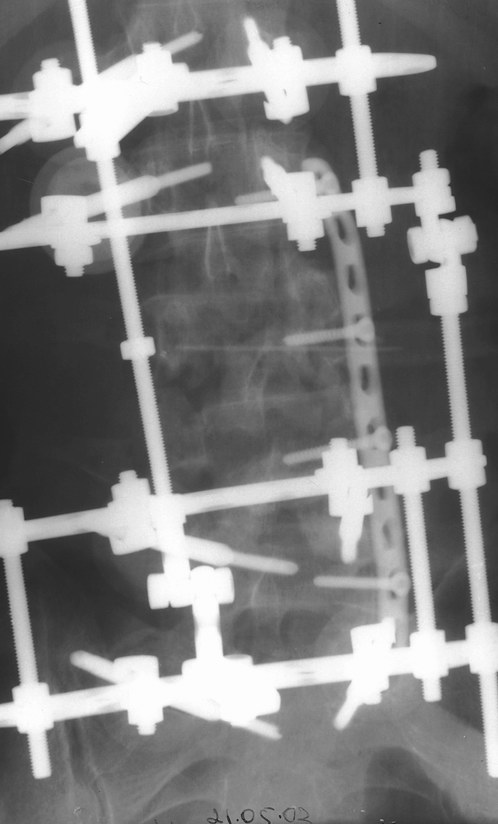

Первым этапом наложен наружный транспедикулярный аппарат, грубая деформация позвоночника устранена. Затем пациент перевёрнут на бок и выполнен забрюшинный доступ по Чаклину. При ревизии обнаружены дислоцированные позвонки "внедрившиеся" в m. psoas. Что интересно, передняя продольная связка хотя и была натянута как струна и отслоена от тел смежных позвонков, но не разорвалась. Ревизия позвоночного канала обнаружила достаточное жизненное пространство для дурального мешка вследствии произошедшей травматической ламинэктомии. Задние отделы повреждённых сегментов переломаны в "крошку". Диск L2-l3 был повреждён поэтому выполнен спондилодез L2-L5. При этом тела 4-го и остатки тела 3-го позвонков использованы в качестве костнопластического метерьяла. Тело 4-го позвонка вертикально и использовано для замещения дефектов на уровне сегментов L3,L4. Для фиксации отломков использована пластина. Стабилность позвоночника обеспечивается АВФ. Неврологическая симптоматика в послеоперационном периоде практически не изменилась. Получает комплексное лечение, планируется в скором времени его вертикализация.